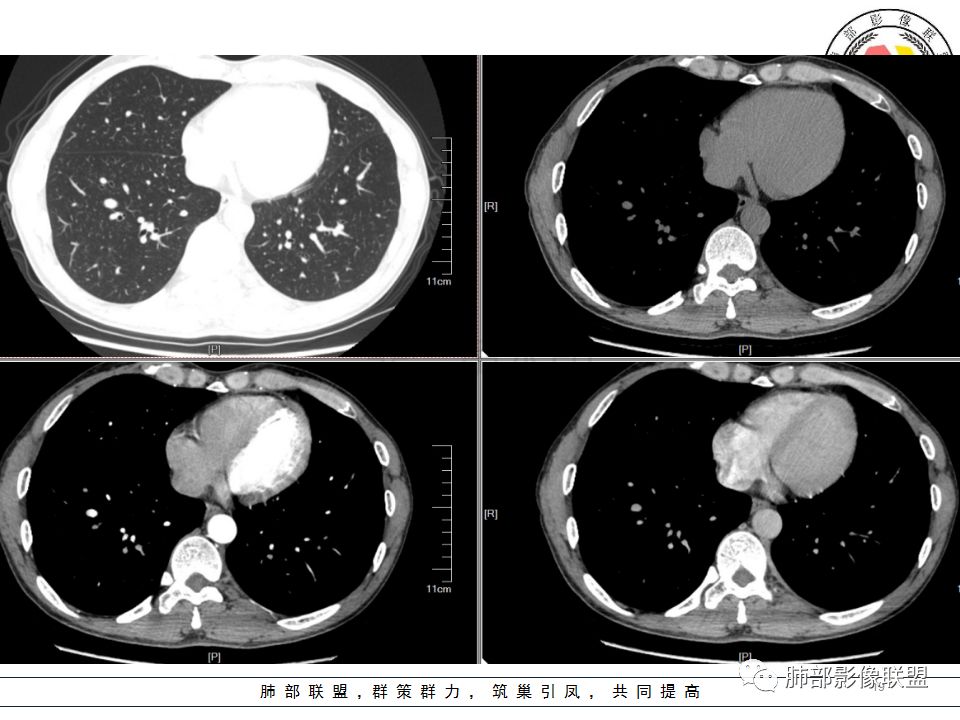

我会做一做支气管的CPR,肺动脉的CPR。

因为南边的考虑一定要看到支气管,怎么办呢?

我很早以前做早癌,就是用CPR技术来观看病灶与支气管、血管的关系。

wonderful:

岁月:

我的重建图像大部分是这样。

360旋转,可以观看意想不到的效果,我一直很重视这两种重建方法。比想象好 直观。